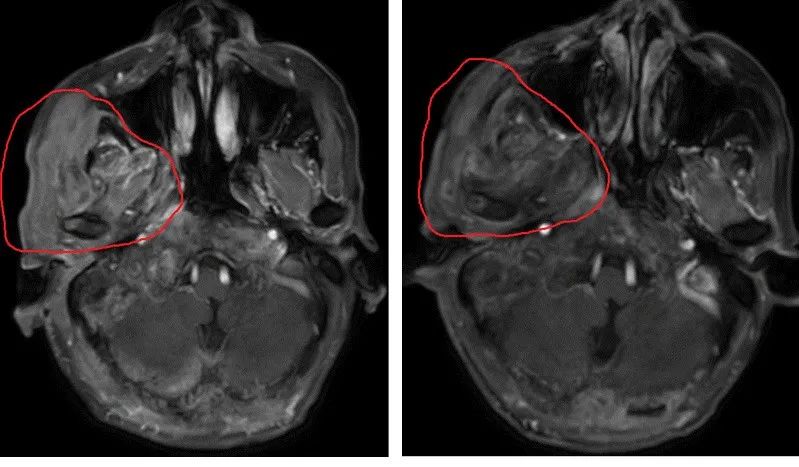

有时候仅仅使用免疫治疗是不够的,有些老年人会需要 把免疫治疗和化疗或放疗结合起来 ,才能取得最佳效果。李阿姨经历的就是这一情况。李阿姨2015年确诊为右扁桃体鳞癌,肿瘤为局部晚期,并伴有淋巴结转移,治疗后完全缓解。2020年再次复发,经多方案、多疗程化疗后,肿瘤进一步增大,病情继续发展。这说明癌细胞对化疗药物产生了耐药。后来,李阿姨接受了免疫治疗+小剂量化疗后,肿瘤逐渐缩小。

患者治疗前后的CT影像